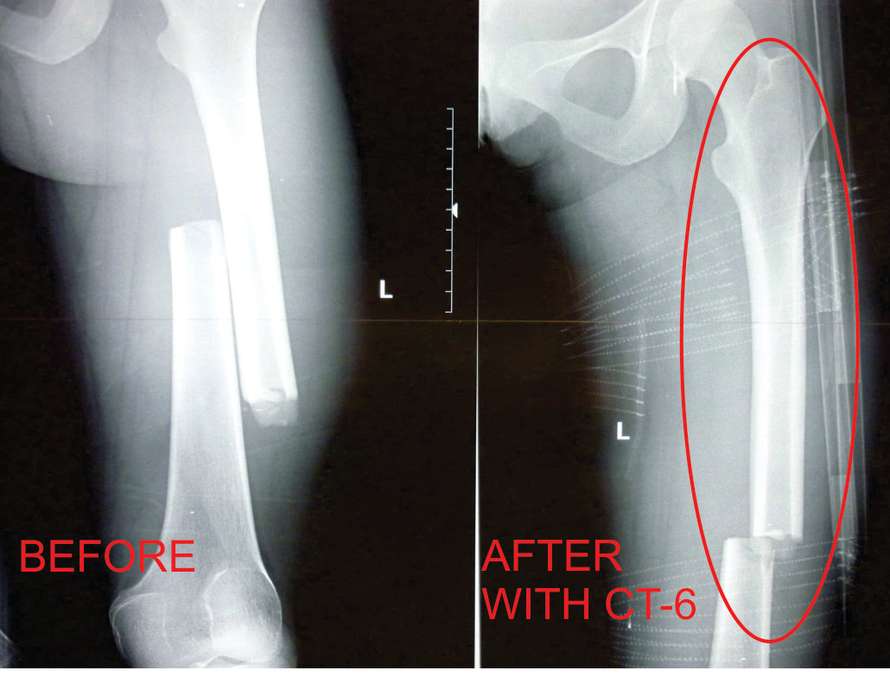

Het team van FareTec Responder Products heeft na twee jaar doorontwikkelen en het verwerken van input van gebruikers van de CT-6 de CT-7 tractiesplint op de markt kunnen introduceren. Voor diverse gebruikersgroepen zijn er voordelen verwerkt, de CT-7 komt bijvoorbeeld niet meer voorbij de voet, is een stuk lichter en in volume kleiner geworden ten opzichte van de CT-6. Er is ook naar gebruikersgemak gekeken, de CT-7 bestaat uit minder bevestigingsbanden en heeft geen losse draden meer, alles is verwerkt in de dikkere carbon buizen. Het tractiemechanisme is simpel, snel en erg precies in te stellen. Het been is tijdens het op tractie aandraaien qua lengte op het oog te vergelijken met het andere been. Door het aandraaimechanisme gaat op tractie brengen zeer beheerst, wat erg prettig is voor de patient in vergelijking tot tractiesplints die met koorden aangetrokken moeten worden. De CT-7 tractiesplint is een welkome vernieuwing op de medic markt.

Verbeteringen ten opzichte van de CT-6:

• Het tractiesysteem komt niet meer voorbij de voet.

• Het op tractie brengen gaat beheerst door het draaimechanisme.

• Versimpeling en meer gebruikersgemak, geen losse draden doordat alles intern is verwerkt!